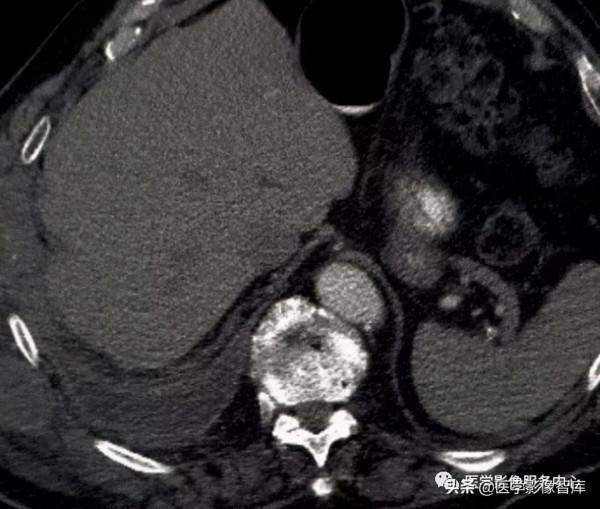

圖24. 薄荷糖徵 A為帶孔薄荷糖;B為左下肺動脈栓塞

薄荷糖徵:⽤於描述垂直於⾎管⻓軸的影象上CT⾎管造影中被造影劑填充的⾎管及部分充盈缺損。類似於薄荷糖,它是⼀種受歡迎的糖果(圖24A),也稱為“帶孔薄荷”。此徵象經典對於肺栓塞(圖24B)的描述,但也可⻅於其他部位的靜脈⾎栓或⻔靜脈⾎栓 等。